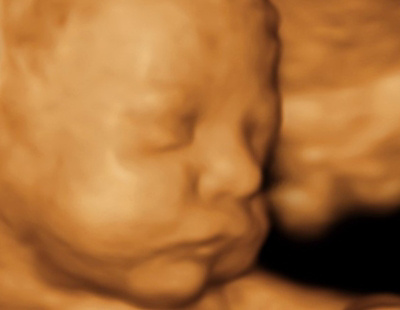

Échographie morphologique

Cet examen est idéalement effectué entre la 20e et la 22e semaine d'aménorrhée et sert à rechercher d’éventuelles malformations fœtales.

A ce stade de grossesse, le fœtus est suffisamment développé pour que nous puissions examiner son anatomie en détail.